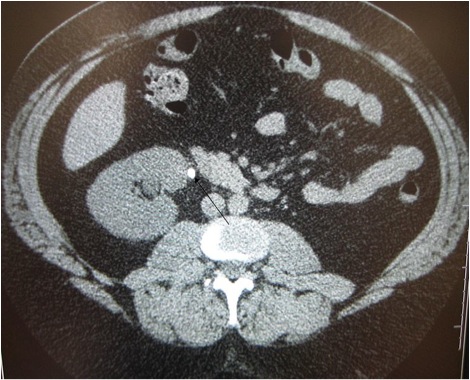

The CT image below shows a patient with a kidney stone obstructing the proximal right ureter. Notice that we can tell the stone is in the proximal ureter because the level of the scan still includes the right kidney. The renal pelvis is just superior to the level of this cross-section.

Kidney Stone on CT Scan